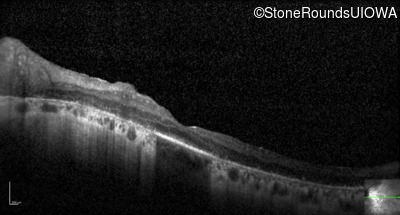

Optical Coherence Tomography - Right - 20/80

Exemplar / OCT Stack

OCT Stack